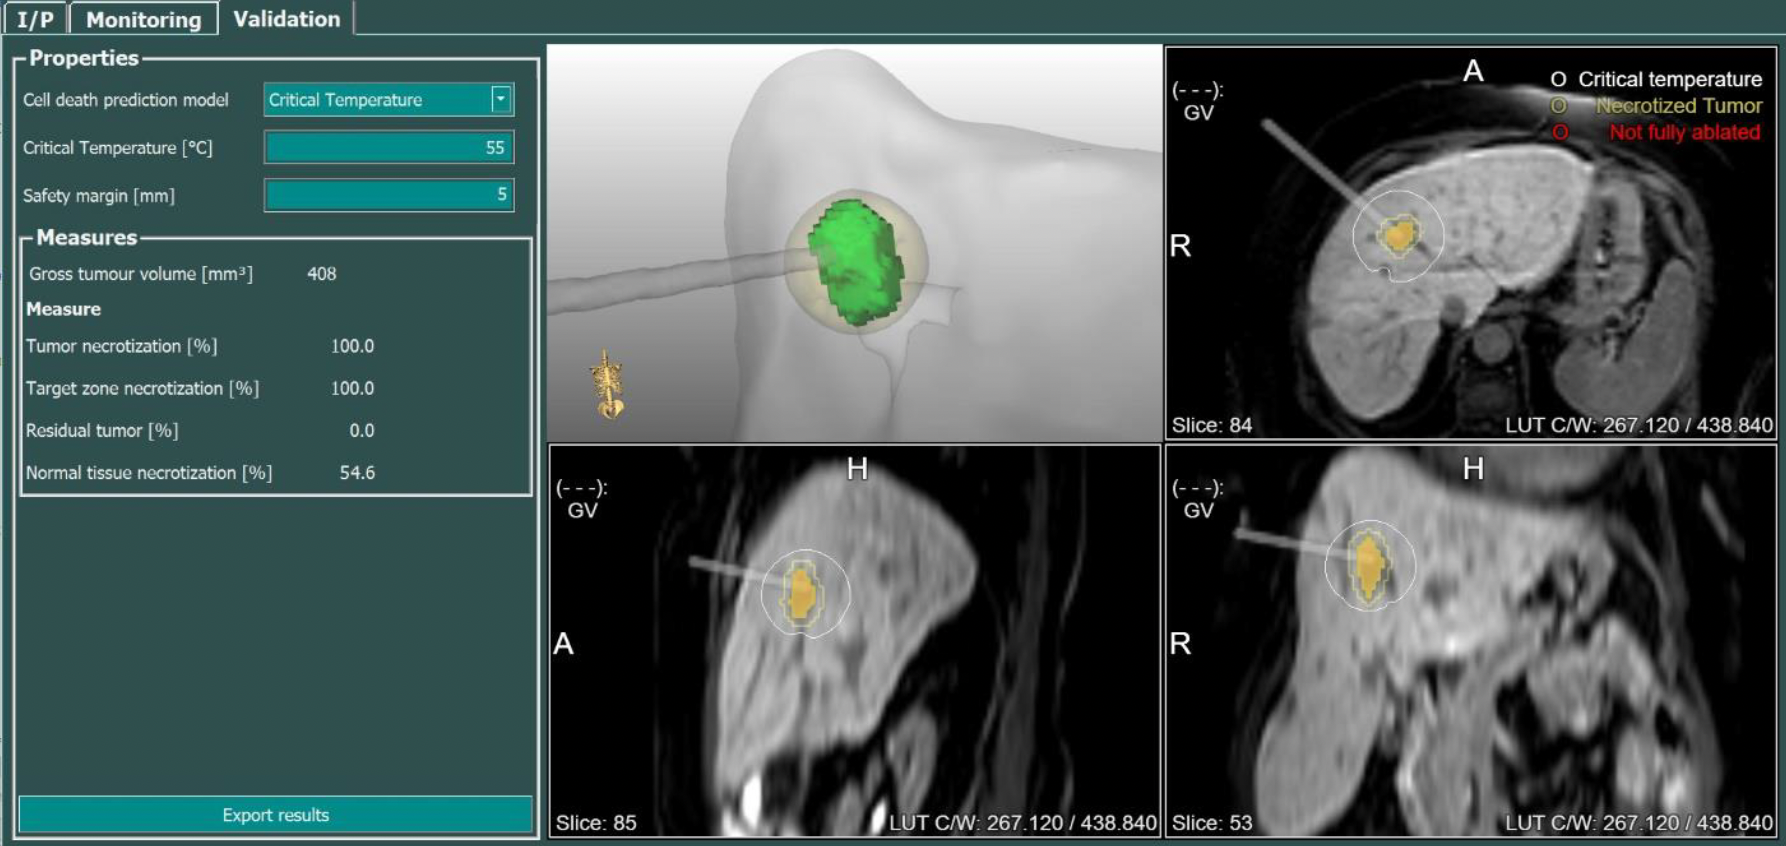

MR-guided percutaneous ablations involve using real-time Magnetic Resonance Imaging (MRI) guidance to perform minimally invasive procedures that destroy or remove abnormal tissue. This technique allows for precise targeting of the tissue to be ablated, such as tumors or lesions, while minimizing damage to surrounding healthy tissue. During the procedure, the MRI scanner provides detailed images that help guide the placement of needles or probes into the target area (Fig. 1). Once positioned, energy, such as microwaves, radiofrequency or laser, is delivered through the needles or probes to heat or destroy the abnormal tissue. Progress of the procedure is monitored by MR-thermometry with so called temperature maps. These maps allow accurate temperature measurements and can be used to predict the destroyed volume ensuring good treatment outcomes (Fig. 2, 3).